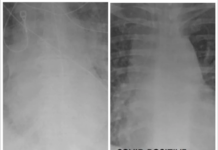

Slika pljuč cepljenega in necepljenega okuženega s COVID-19

Ameriški zdravnik dokazal, zakaj se je treba cepiti proti covidu-19!

Vodja enote za intenzivno nego v univerzitetni bolnišnici St. Louis Gasan Kamel je predstavil sliko...